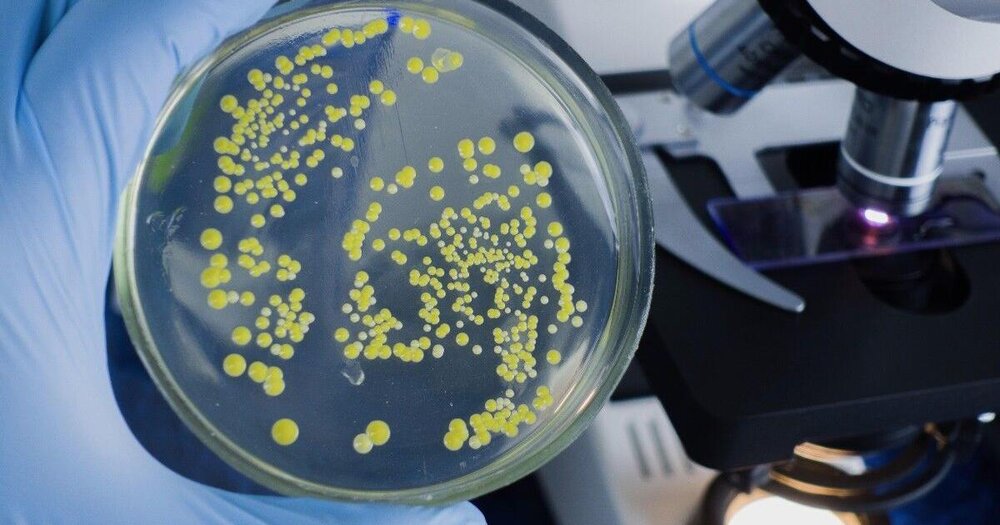

سندرم شوک سمی استرپتوکوک در حال گسترش در ژاپن

وبگردی/خراسان رضوی مقامات کشور ژاپن اعلام کردند که عفونت باکتریایی کشنده به نام سندرم شوک سمی استرپتوکوک (STSS) همچنان در…

سندرم شوک سمی استرپتوکوک در حال گسترش در ژاپن

وبگردی/خراسان رضوی مقامات کشور ژاپن اعلام کردند که عفونت باکتریایی کشنده به نام سندرم شوک سمی استرپتوکوک (STSS) همچنان در…